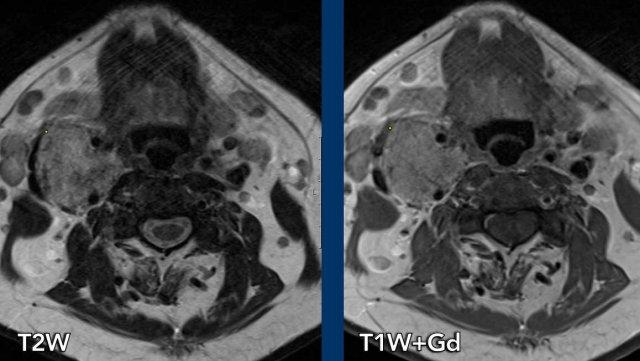

Hình ảnh

Có một tổn thương trong khoang cảnh tại vị trí chỗ chia đôi làm doãng rộng động mạch cảnh trong và động mạch cảnh ngoài.

Trên T2W tổn thương tăng tín hiệu và trên T1W đồng tín hiệu với hình ảnh muối tiêu.

Có ngấm thuốc sau tiêm tương phản (hình ảnh không được trình bày).

Continue with the Twist-MRA images…

Trên chuỗi xung TWIST MRA có thấy ngấm thuốc thì động mạch sớm tại tổn thương lớn bên phải.

Lưu ý rằng ở bên trái cũng có một tổn thương ngấm thuốc thì động mạch sớm tại vị trí chỗ chia đôi động mạch cảnh.

Kết luận

U cận hạch hai bên.

Tổn thương hai bên thường gặp trong các hội chứng di truyền như đột biến gen SDH.